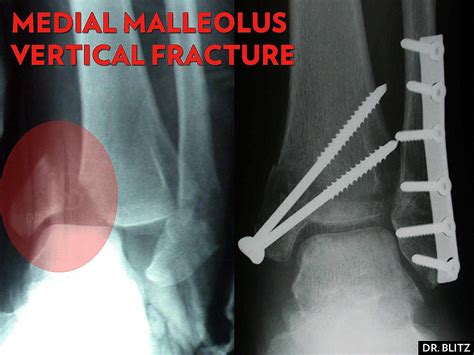

• X-rays: Standard X-rays can reveal the presence and extent of the fracture. Multiple views may be taken to get a comprehensive picture.

For more severe fractures, especially those involving displacement or multiple fragments, surgery may be necessary. Surgical options include:

• Open Reduction and Internal Fixation (ORIF): This procedure involves realigning the bone fragments and securing them with plates, screws, or rods.